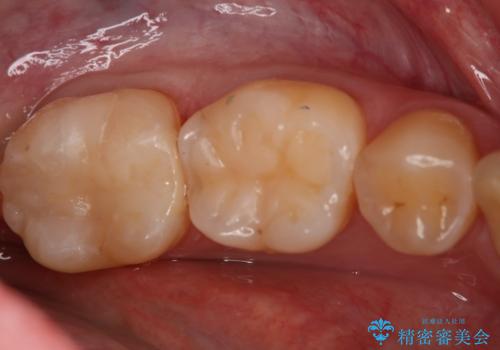

精密根管治療を行なったことで病巣は消失し、腫れや痛みは再発することなく経過は良好です。

被せ物はフルジルコニアクラウンを選択されました。